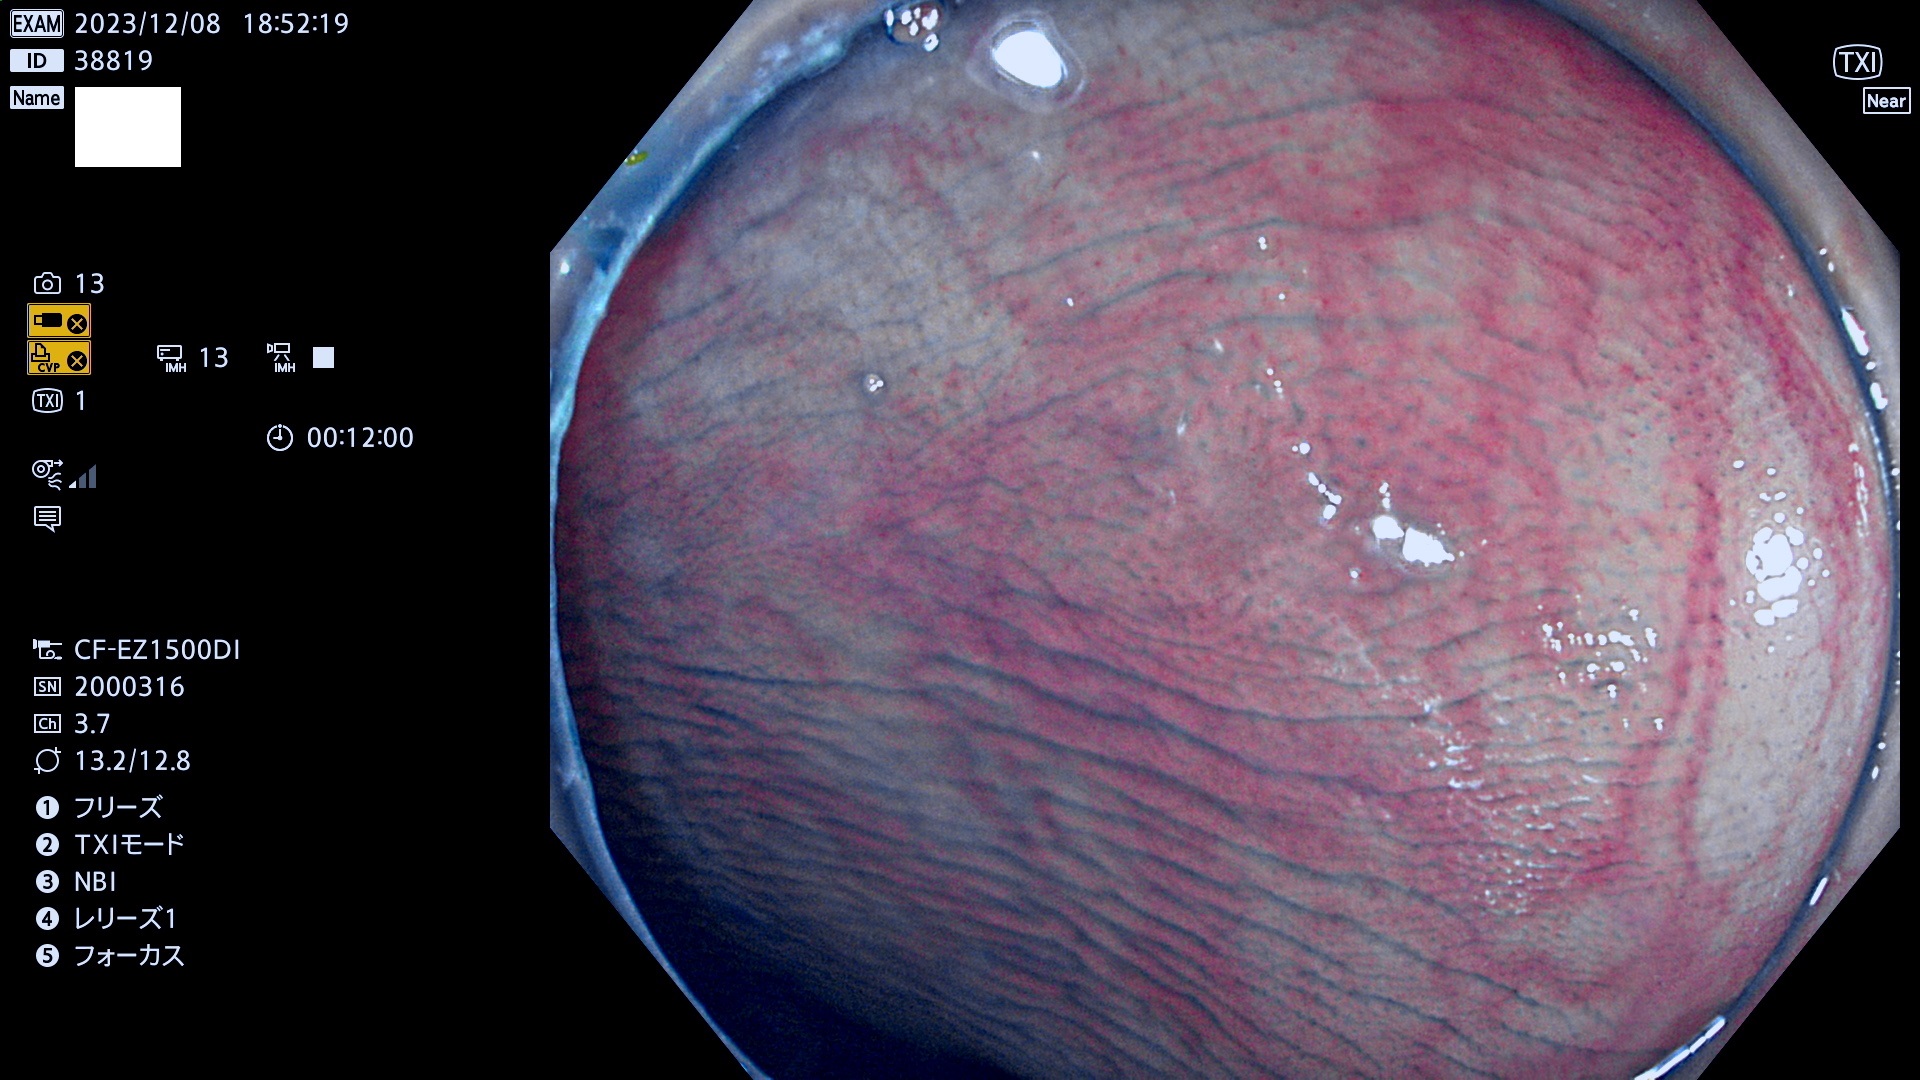

表面型腺腫(Flat Adenoma)の中で、完全に平坦な物をUb、陥凹している物をUcと呼びます。平坦隆起型(Ua)よりも、発見が難しく危険な病変です。このタイプは「内視鏡後・大腸癌の重要犯人」であり、この発見率は「腺腫発見率」よりも、重要な意味があります。

毎週の検査(木・金・土・日)に発見されたUb、Uc型・腺腫を、その週の日曜の夜にUPし1週間、提示します。

抽出の対象期間 2023年12月7日(木)〜12月10(日)の4日間(48件の検査)12件